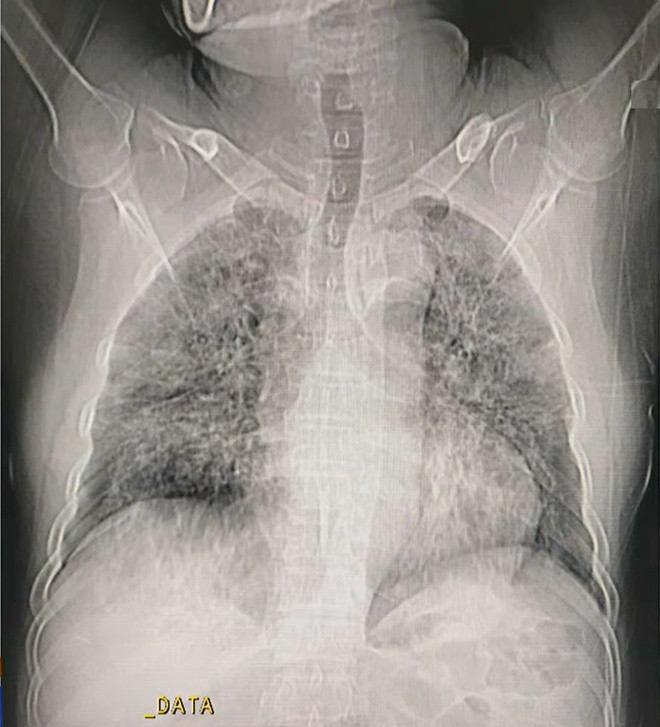

Hình ảnh phổi người mắc Covid-19 ở Việt Nam ảnh 1

Hình ảnh phổi của ca mắc Covid-19 thứ 867, các tổn thương cho thấy người này ở giai đoạn đỉnh bệnh. - Ảnh: Bệnh viện Đại học Y Hà Nội.

Ở giai đoạn sớm (0-4 ngày sau khi xuất hiện triệu chứng), X-quang phổi cho thấy kính mờ, hình lát đá, thùy tổn thương ít.

Đến ngày 5, phổi có kính mờ, hình lát đá lan rộng hai bên. Tình trạng này kéo dài đến ngày thứ 8 và được gọi là giai đoạn tiến triển.

Ở giai đoạn đỉnh bệnh (sau 10-13 ngày), phổi của người mắc Covid-19 xuất hiện các vùng đông đặc. Đây cũng là thời điểm cơ quan này bị tổn thương nhiều nhất.

Từ ngày thứ 14 trở đi, nếu bệnh nhân nặng, phổi tiếp tục đông đặc hơn, thậm chí kèm bội nhiễm lan tỏa hai bên. Với những người chữa trị hiệu quả, thời gian này phổi sẽ bước vào giai đoạn thoái triển, dải xơ dưới màng phổi giảm, giãn phế quản ngoại vi.